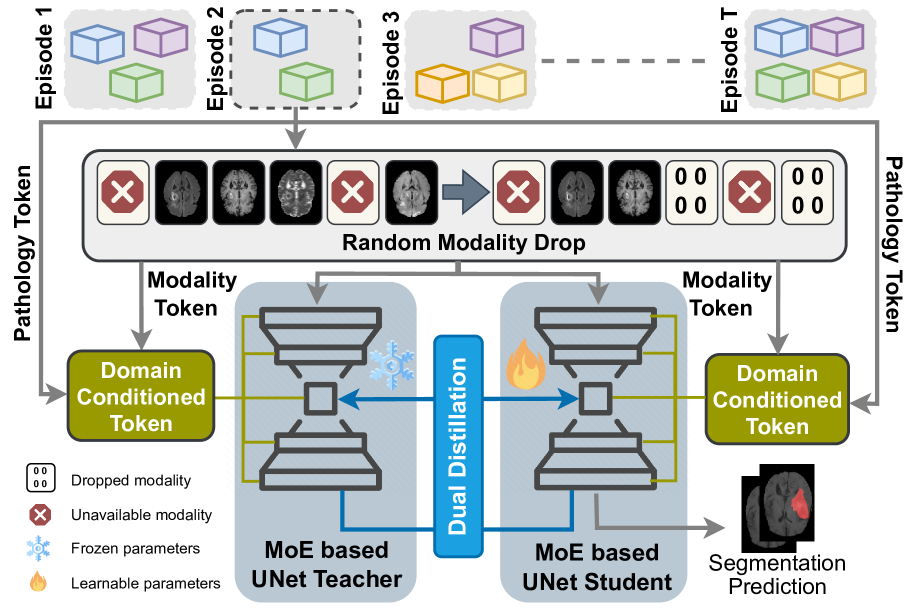

2 Methodology

In CL, a model sequentially learns datasets (), each differing in disease type, modalities, and data sources. At any time , only the training set of is available, while test sets from all past datasets remain accessible. To prevent catastrophic forgetting without storing past data, we use a buffer-free approach essential for privacy-sensitive applications. Our method employs dual knowledge distillation, where the previous model (teacher, ) guides the current model (student, ), ensuring knowledge preservation while learning new data. We also integrate a domain-conditioned MoE in convolution layers to minimize interference. The training combines a segmentation loss on the current dataset with dual distillation losses from the teacher model. Additionally, random modality dropout enhances generalization by exposing the model to different modality combinations. A flowchart of our approach is shown in Fig. 2. The next sections detail handling modality variations and our buffer-free CL strategy.

2.1 Variable modality handling

Segmentation datasets in a sequence () often have distinct MRI modality sets (), where represents the modalities available in dataset . Training with requires a UNet with input channels, necessitating a separate UNet for each unique modality set. However, for continual learning across datasets, a single model must handle all modality variations. A simple yet effective solution [Xu et al.(2024)Xu, Moffat, Seale, Liang, Wagner, Whitehouse, Menon, Newcombe, Voets, Banerjee, et al.] uses a single UNet with input channels set to the maximum number of expected modalities , representing possible modalities as . This design ensures compatibility with all datasets having . If a modality is missing in a dataset, the corresponding channel is zero-filled. To improve generalization and mitigate spurious correlations between datasets and modalities, we employ random modality dropping during training. This exposes the model to varied modality combinations from each dataset, enhancing robustness. While this approach enables handling variable modalities within a unified framework, it is expected to slightly underperform compared to dedicated UNet models tailored for individual datasets.

2.2 Dual distillation

We propose a dual Knowledge Distillation (KD) strategy, transferring knowledge from the teacher to the student model at both latent features and response outputs. This dual alignment preserves structural and contextual information across hierarchies, enhancing the model’s ability to retain learned knowledge. In the response-based KD [Li et al.(2024)Li, Su, Zhang, and Wang], student model is enforced to produce similar output (response) as the teacher model. Typically, KL-divergence between the teacher and student model outputs on current data is used as a regularization term, defined as:

| (1) |

where is KL-divergence, and are the output logits for input by and , is softmax operator applied to obtain soft targets for KD with temperature . Instead of using a static regularization coefficient as in prior works [Li and Hoiem(2018), Kirkpatrick et al.(2017)Kirkpatrick, Pascanu, Rabinowitz, Veness, Desjardins, Rusu, Milan, Quan, Ramalho, Grabska-Barwinska, et al.], we propose a dynamic coefficient () for , that adapts based on the degree of domain shift between datasets. Greater shifts necessitate stronger regularization to mitigate forgetting. The shift is estimated using the inverse of the Dice Similarity Coefficient (DSC) on unseen data, scaled to a user-defined range as . This dynamic adjustment accounts for variability in dataset distributions, ensuring effective KD.

To complement response-based KD, we add latent-based KD [Li et al.(2024)Li, Su, Zhang, and Wang], which targets the alignment of latent representations between the student and teacher models. To achieve this, we employ a cosine similarity-based regularization loss, , which aligns the latent feature representations of the student model with those of the teacher model

| (2) |

where and represent flattened bottleneck features from the teacher model and student model , respectively.

2.3 Mixture-of-Expert

When learning a new dataset naively, the model often overwrites previously acquired weights, leading to poor performance on old data. To address dataset conflicts, generic CL literature has mainly explored adding parameter subsets or reserving parameters in fixed networks [De Lange and Tuytelaars(2021)]. However, parameter addition can cause unbounded model growth, while hard reservation restricts knowledge sharing across datasets. To overcome these issues, we draw inspiration from soft parameter reservation techniques in multi-task learning [Shazeer et al.(2017)Shazeer, Mirhoseini, Maziarz, Davis, Le, Hinton, and Dean], which enable flexible capacity sharing across tasks. Specifically, we propose integrating a domain-conditioned MoE mechanism into each convolutional layer of the UNet model. This approach dynamically activates experts with varying strengths based on the domain, achieving soft parameter isolation in a fixed parameter network. The MoE uses a domain-conditioned token derived from dataset-specific metadata to compute gating weights via a linear gating network, , where is softmax operation, and are the gating network’s parameters for number of experts, and is a domain-conditioned token concatenating binary representations of available modalities and disease , with and being maximum number of allowed modalities and pathology. This design ensures that each domain is handled uniquely, enabling the model to adaptively allocate expertise. Finally, the gating weights, , are used to aggregate outputs from experts, , as: , where is the input feature map, is the expert, and is the aggregated output. Unlike hard expert selection, our MoE employs soft selection, allowing contributions from all experts while dynamically adjusting their influence based on the dataset context.

2.4 Model objective

The student model is trained with joint supervision from the teacher model and current data, enabling it to perform effectively on both previously seen and newly introduced data. At any session , the student model is optimized using a total loss , comprising segmentation loss (), cosine similarity loss (), and KL-divergence loss (). The segmentation loss integrates Dice loss (Dice) and cross-entropy loss (CE), as commonly adopted in literature [Sadegheih et al.(2024)Sadegheih, Bozorgpour, Kumari, Azad, and Merhof]. This multi-component loss enables the model to balance between learning new information and retaining prior knowledge:

| (3) |